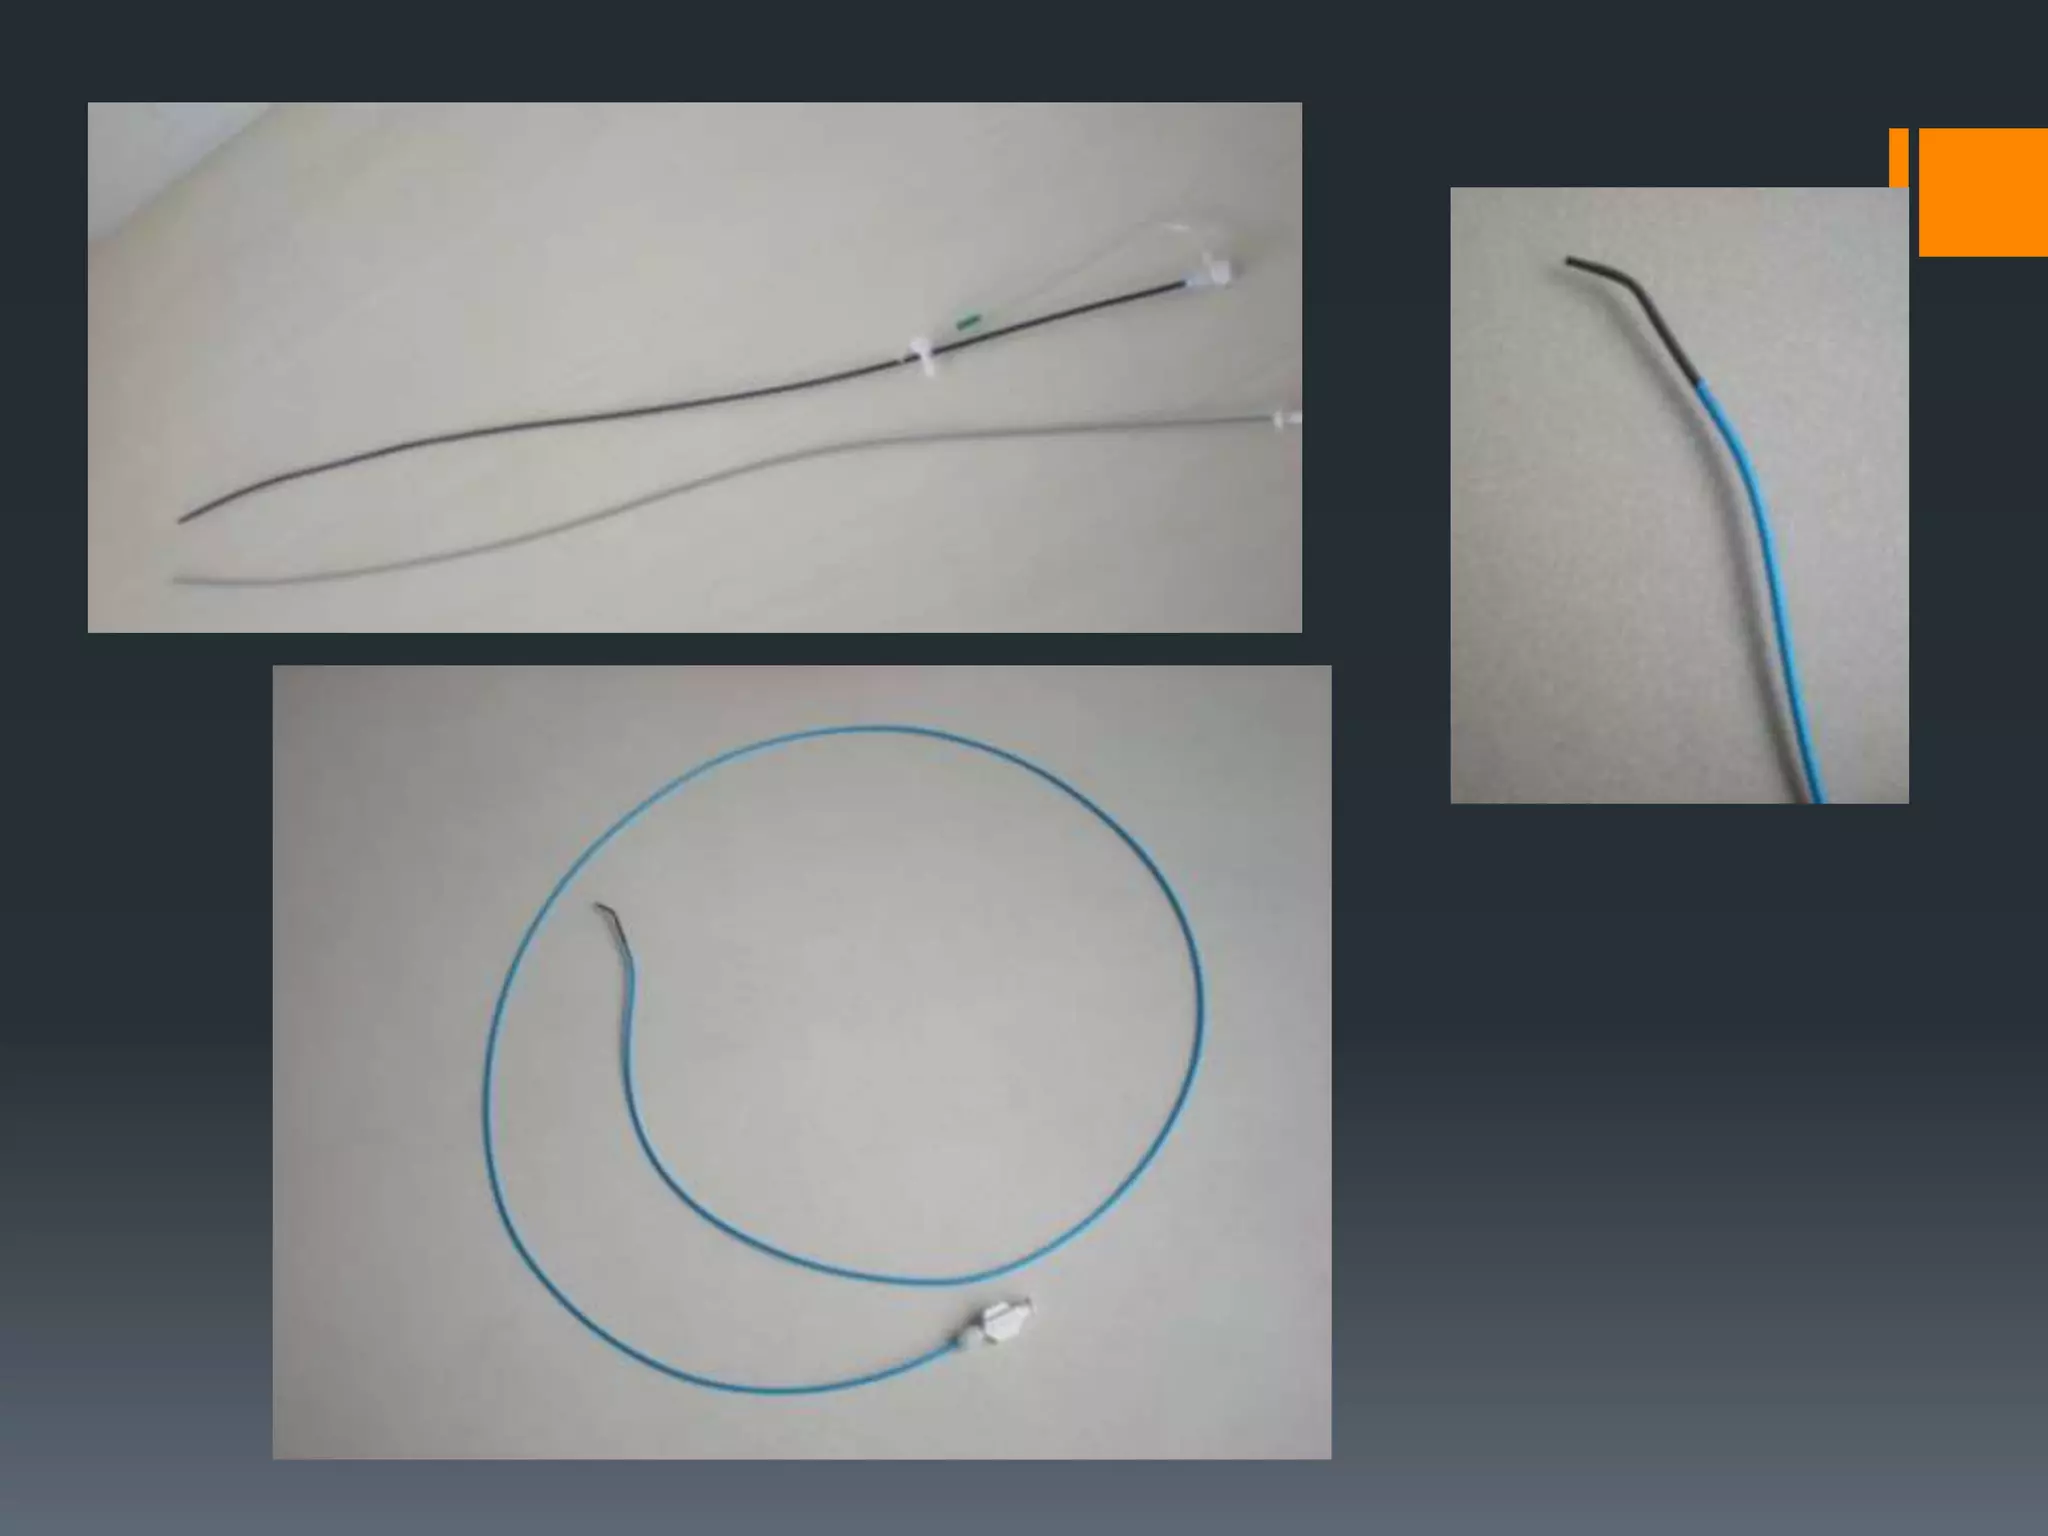

This document discusses tricks and techniques for difficult cannulations during neurointerventional procedures. It outlines strategies for accessing the aortic arch, internal carotid artery (ICA), and areas distal to aneurysms. Long sheaths, distal access catheters, and co-axial techniques are presented as options that have improved cannulation success. Guidance on sheath and catheter selection is provided for different vessel paths. The importance of catheter placement as high as possible in the ICA is emphasized. Reverse curve cannulations are also mentioned. Overall, the document stresses that careful cannulation is critical for procedural success and different strategies may be needed depending on the vessel target.